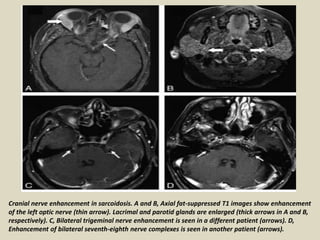

Cranial nerve involvement: Cranial nerves are affected in up to 50% of patients with

neurosarcoidosis. There is poor correlation between imaging findings and clinical

symptoms. While facial nerve deficits are most commonly found clinically, the optic nerve is

the most common cranial nerve to appear abnormal on MRI. Affected cranial nerves show

enhancement and thickening with or without associated leptomeningeal involvement.

Cranial nerve enhancement in sarcoidosis. A and B, Axial fat-suppressed T1 images show enhancement

of the left optic nerve (thin arrow). Lacrimal and parotid glands are enlarged (thick arrows in A and B,

respectively). C, Bilateral trigeminal nerve enhancement is seen in a different patient (arrows). D,

Enhancement of bilateral seventh-eighth nerve complexes is seen in another patient (arrows).